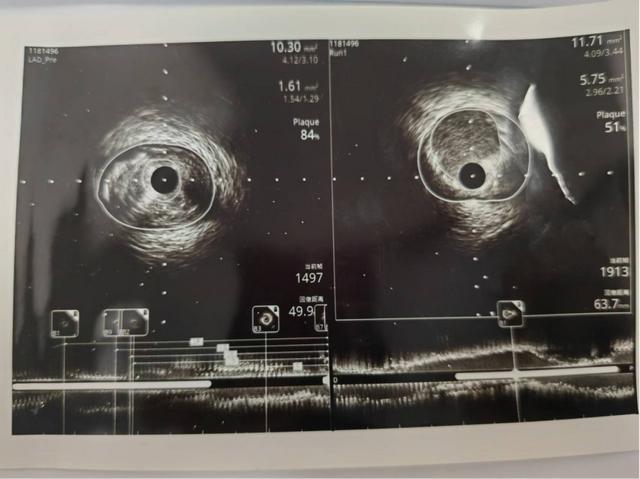

术中IVUS超声提示前降支近段斑块负荷84%,最狭窄处管腔面积1.61mm2,在IVUS指导下完美扩张了病变,成功植入支架后复查,IVUS提示支架膨胀、贴壁良好,无夹层,原最狭窄处管腔有效面积5.75mm2。

(术前IVUS与术后IVUS)